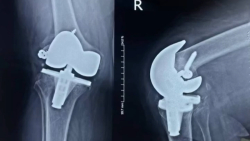

عمل تعویض مفصل دو زانو

تعویض مجدد مفصل زانو

فیلم مراحل تعویض مفصل زانو